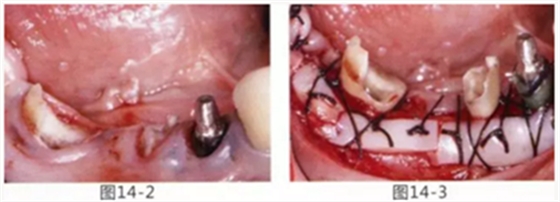

病例5

為了提高對修復體的術后效果,以生物學寬度,獲取附著齦為目的進行游離齦移植的病例

圖14-1 修復體周圍角化牙齦較少,很難進行清潔的狀態(tài),并有緣下齲壞的發(fā)生。

圖14-2,3 徹底去除齲壞后,試圖通過游離齦移植獲取生物學寬度和附著齦。

圖14-4~6修復體周圍角化牙齦較少,很難進行清潔的狀態(tài),并有緣下齲壞的發(fā)生。

圖14-7 配戴最終修復體完成5年后的狀態(tài)。保持良好。